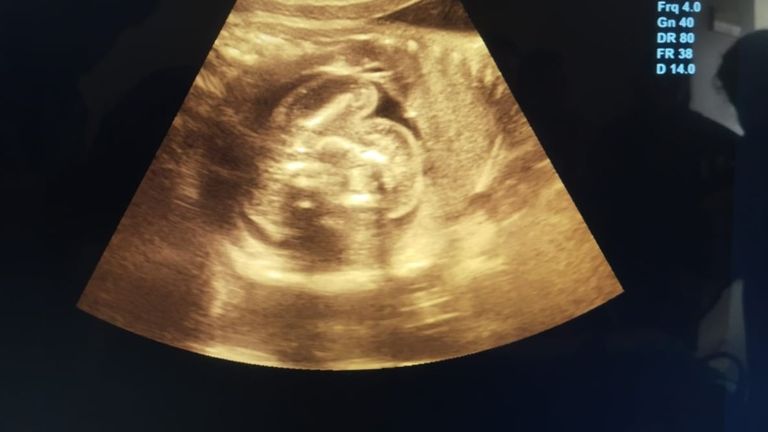

इस मामले की पुष्टि करने वाले डॉक्टर के.के. गुप्ता, जो एक रेडियोलॉजिस्ट हैं ने कहा कि इतने सालों के वो इस काम को कर रहे हैं लेकिन उनके करियर में ऐसा केस पहली बार आया है. पूरी दुनिया में अभी तक ऐसे सिर्फ 18 केस ही सामने आए हैं और भारत में यह पहला मामला हो सकता है.

महिला पहले से दो बच्चों की मां है और एक सामान्य गृहिणी है. वहीं उसके पति एक प्राइवेट कंपनी में जॉब करते हैं. डॉक्टरों का कहना है कि इस तरह की प्रेग्नेंसी को मेडिकल भाषा में एब्डोमिनल प्रेग्नेंसी कहा जाता है, जो बेहद खतरनाक होती है.

डॉ. गुप्ता ने आजतक को बताया, ''22 जुलाई को जब महिला इस केस को लेकर आई और जब इस एबनॉर्मल प्रेग्नेंसी का खुलासा हुआ तो हमने मेडिकल लिटरेचर खंगाला और पता चला की लीवर में भ्रूण होना बहुत ही दुर्लभ है और 14 हफ्ते से ज़्यादा इसे रखना मां के लिए जानलेवा साबित हो सकता है."